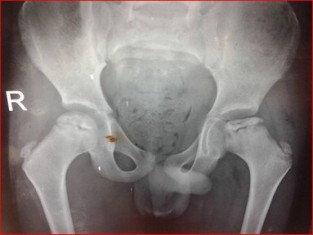

Diagnosing Perthes Disease involves a combination of clinical evaluation, medical history assessment, and imaging studies. X-rays and MRI scans are commonly used to confirm the diagnosis and determine the extent of bone damage.

Perthes Disease, also known as Legg-Calvé-Perthes Disease, is a rare childhood condition that affects the hip joint. It occurs when there is an interruption in the blood supply to the ball-shaped head of the thigh bone (femur), leading to the deterioration of the bone tissue. This can result in pain, limited mobility, and other hip-related issues in children..